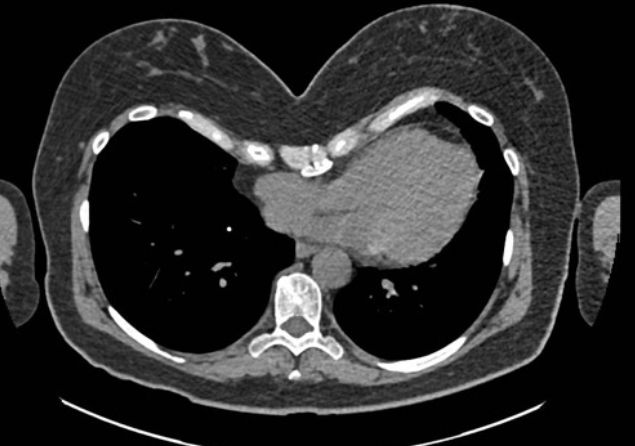

JC, 62-year-old with severe pectus excavatum and significant physical symptoms.

Chest CT before surgery showing severe pectus excavatum with Haller index 4.5